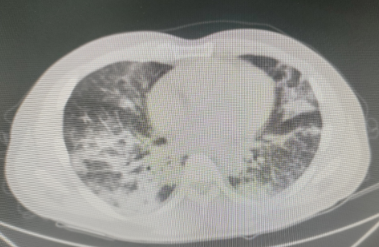

龙先生,36岁,在浙江务工,与朋友一行数人到树林捕捉竹鼠。回老家花垣县后即出现了发热、咳嗽、乏力等症状,他一开始没有特别在意。几天过去了,症状一点也没有缓解,并出现了胸闷、气短,便来到花垣县人民医院就诊。医生为他安排胸部CT检查,结果显示,他的双肺出现了弥漫分布斑片状增高影,边缘模糊。结合患者临床症状、胸部影像学和流行病学史,医生高度怀疑他很可能是感染了特殊病原体,于是为他进行了支气管镜检查,留取肺泡灌洗液送检病原体靶向测序。检测结果出来,确诊为马尔尼菲篮状菌感染,其序列数高达10190,医生立即为龙先生进行抗真菌、对症一系列治疗,肺部炎症逐渐吸收,阴影缩小。

检病原体靶向测序结果确诊为马尔尼菲篮状菌感染